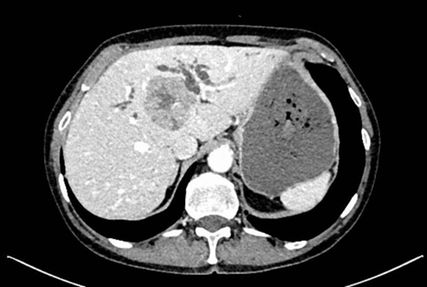

Die initiale CT zeigte eine bis zu 6cm große Raumforderung, ausgehend von der Hepatikusgabel, mit zentraler Infiltration des Leberparenchyms, suspekten Lymphknoten im Leberhilus und retroperitoneal, deutlich dilatierten intrahepatischen Gallengängen sowie Umscheidung und Infiltration des linken Pfortaderastes, jedoch ohne Thrombose. Der Befund war hochverdächtig auf einen cholangiozellulären Tumor. Die histologische Aufarbeitung einer Punktionsbiopsie ergab jedoch ein gering differenziertes, hiläres hepatozelluläres Karzinom (WHO 2019: G3). Angesichts des bildgebenden Befundes und des ebenfalls erhöhten Ca19-9 stand der Verdacht auf einen Mischtumor im Raum.

In der durchgeführten Staging-CT zeigte sich ein partielles Ansprechen (PR) mit Tumorgrößenreduktion von 49mm auf 33mm, die Lymphknoten blieben unverändert. Die Tumormarker sanken (AFP: 150, Ca19-9: 65). Aufgrund der persistierenden Diarrhö und des Verdachts auf einen Mischtumor erfolgte eine Umstellung der Therapie auf Cisplatin/Gemcitabin/Bevacizumab, wobei Gemcitabin ab Zyklus 2 wegen Fatigue auf 75% reduziert wurde und Cisplatin ab Zyklus 3 aufgrund von Ototoxizität abgesetzt werden musste. Nach vier Zyklen zeigte die MRT ein weiteres partielles Ansprechen (19×21mm), die Lymphknoten waren unverändert, die Tumormarker normalisierten sich erstmals.

Bildgebend können sich Mischtumoren wie ein HCC-iCCA-Gemisch imponierend darstellen, wie ein typisches HCC oder aber ein typisches iCCA aussehen oder sich unspezifisch darstellen. Bildgebende Hinweise auf Mischtumoren bestehen bei verschiedenartigem Kontrastmittelverhalten innerhalb eines Tumors (im Verlauf zunehmende Anreicherung, Anreicherung mit Wash-out, Anreicherung ohne Wash-out oder Hypovaskularisierung), vaskulärer Invasion und Gallengangsbeziehungen. Die Kombination erhöhter Tumormarker (AFP und Ca19-9) kann einen Hinweis liefern, ist aber nicht beweisend.